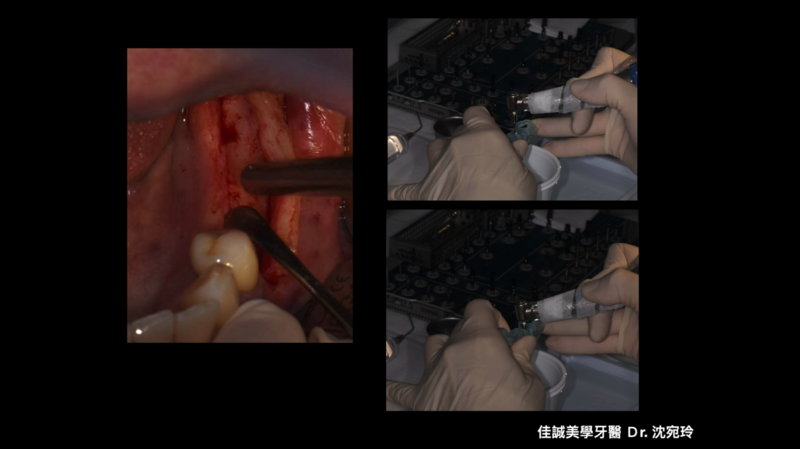

治療的開始是我們幫病患解決了疼痛,從病患腫痛,拆假牙、拔牙,恰好左下第一小臼齒為根管難症,仰賴錢正原醫師的成功顯微根管治療,取的病患的信任。接著我們一步步的重建,也因為這區是長達十幾年的五單位牙橋,拆掉後除了病患明顯左邊不好咀嚼,因此對於重建有強烈的企圖心,另外我們也看到因為長久缺牙而有牙脊萎縮,並伴隨角質化上皮缺損。缺損的骨頭部分我們是補得回來的,但一次三顆植體加上水平補骨,若在缺角質化上皮的這區手術,總覺得風險高了些。因為若有足夠的角質化上皮,可以讓我們植牙手術補骨縫合時,將縫線進針在角質化上皮內,縫線與角質化上皮內就像釘書針扎實的釘錨著,能對抗術後腫脹期防止傷口裂開,讓手術更能保證成功; 另外,若於其後補上骨粉和再生膜後,牙脊上的角質化上皮也相對穩定,不會在咀嚼時移動,讓其下方的骨粉可以好好轉換成自體骨; 角質化上皮的功能不只如上,在將來植體接假牙出來後,在咀嚼時,也因有足夠角質化上皮的包覆,能防止食物掉入和植體相接的牙肉內,防止植體周圍炎的產生。談到植體周圍炎的預防,植體植入的位置,最好平行假牙咬合軸向的受力,並且出孔位置在假牙的正中心。

以這個案例,我們量測了牙脊缺牙區的總寬度,再精算植體間距和植體寬度,後牙區小臼齒種植寬度長度4 mm X 11.5mm的植體,大臼齒則置入兩支寬度長度5 mmX11.5mm的植體,而在設計時在軟體內要讓三顆植體盡可能平行,以利將來植牙贋復製作,減少應力集中造成植體周圍炎的可能。我們利用模子的STL檔和斷層掃描的DICOM檔做疊合,在Bluesky軟體內,由醫師自己設計出最佳的植體位置、寬度長度,再請專業的3D列印公司做數位模板輸出。因為在軟體內我們已經看出將來植體的位置和需補骨的量,進而反推切線的位置,最後我們知道角質化上皮終究都需要補一場,於是治療計畫一開始就是先補上角質化上皮,等四個月後軟組織穩定,我們接著利用手術導板植入三個植體,並於當次補入骨粉和再生膜,術後如我們預期,傷口恢復良好。